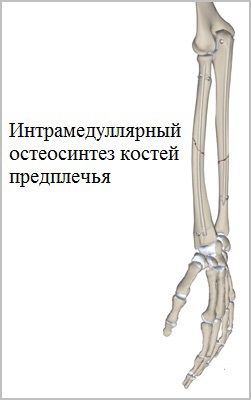

Pentru tratamentul fracturilor antebratului folosind diferite tipuri de elemente de fixare. De exemplu, blocate intramedulare tije (intraosoase) utilizate în fracturile de rază și cubitus diafizare osului și permit obținerea unor fixare stabilă cu un prejudiciu minim de țesuturi moi.

Cicatricile dupa astfel de operațiuni este atât de mică dimensiune care observă nu este întotdeauna posibil, chiar și pentru un expert.